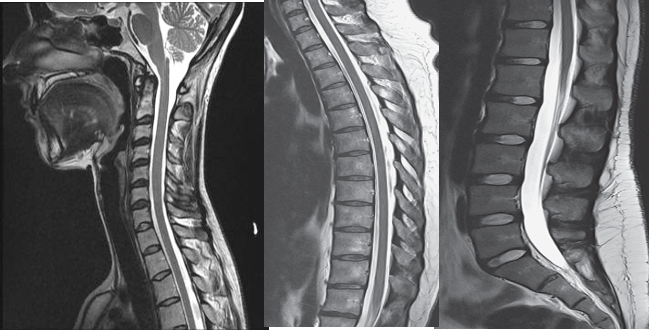

The gold standard of imaging for spinal disorders

Can identify abnormalities of bone, discs, muscles, ligaments and spinal cord

Intravenous contrast is sometimes administered to better visualize certain structures or abnormalities